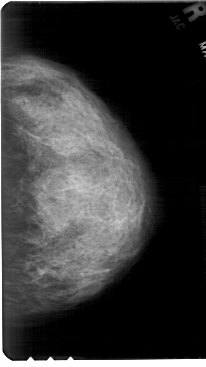

A_1678_1.RIGHT_CC

RIGHT_CC LINES 5491 PIXELS_PER_LINE 3076 BITS_PER_PIXEL 12 RESOLUTION 43.5 NON_OVERLAY